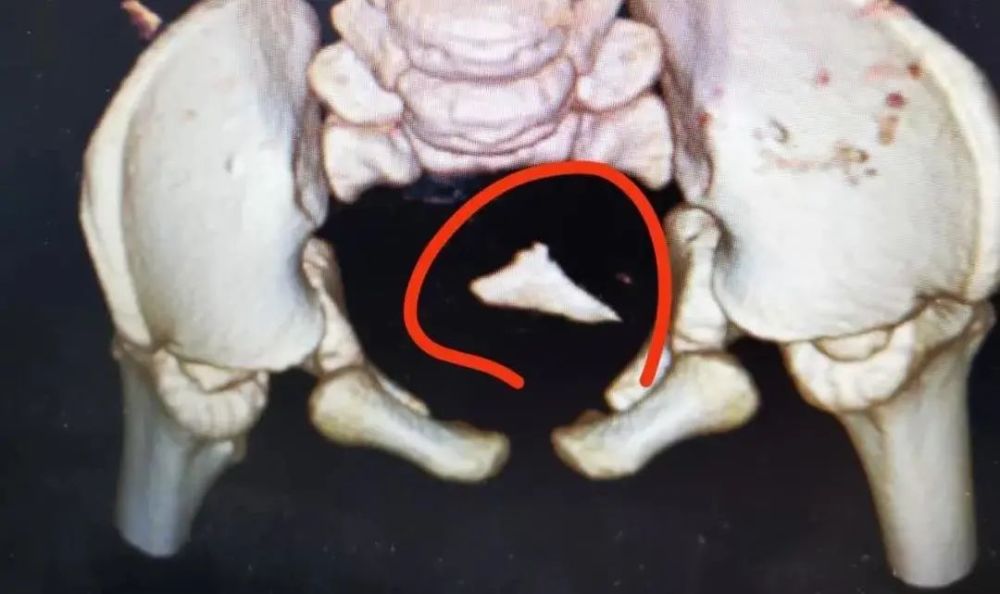

当医生重新为阳阳进行CT检查时,异物并没有如家长所愿自行排出,而是卡在了乙状结肠处,形状类似于三角形,还有些尖锐。

“我们接诊过很多类似的病例。”张志华说,“阳阳的血便可能就是肠道被异物的尖锐处划伤了,为防止异物造成肠道穿孔,因此尽快安排手术取出了鱼骨,孩子脱离了危险。”